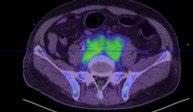

B: No obvious bone destruction. Soft tissue in lower abdomen, with increased metabolic activity: EMD?

• PET CT after 6 months of teclistamab (1/2024)

• previous R NP mass, cervical LN, R hilar mass, peritoneal mass, peritoneal deposit, paraspinal soft tissue mass, epidural mass from T9-11 resolved